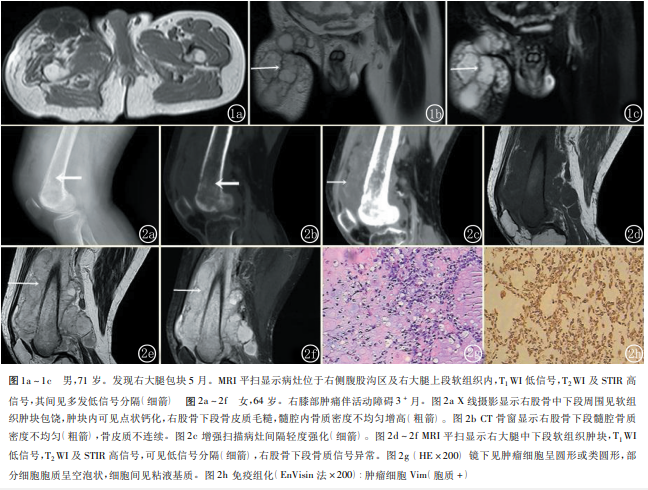

例 1:MRI 平扫 表现为右侧腹股沟区及右大腿上段前方软组织内多发不规则分叶状异常信号影( 图 1a) ,T1WI 低信号, 部分信号不均匀,T2WI 高信号,STIR 呈高信号,其内分隔呈低信号( 图 1b,1c) ,邻近肌群受压、移位, 骨质信号未见异常。

例 2 :X 线摄影表现为右股骨中下段周围见软组织肿块影,内见点状钙化,骨皮质毛糙,可见层状骨膜反应,髓腔内密度不均匀增高 ( 图 2a) 。CT 显示右股骨中下段周围见不规则软组织肿块,包绕右股骨生长,右股骨中下段骨质密度不均匀,见多发筛孔状骨质破坏区( 图 2b) ,增强扫描病灶实性成分不均匀轻度强化,内见多发血管影及斑片状无强化区( 图 2c) 。MRI 表现为不规则软组织肿块包饶右股骨中下段,T1WI 呈等信号,T2WI 及 STIR 呈高信号,内见多发低信号间隔( 图 2e,2f) ,右股骨中下段骨质信号异常,T1WI 低信号,T2WI 及 STIR 高信号。